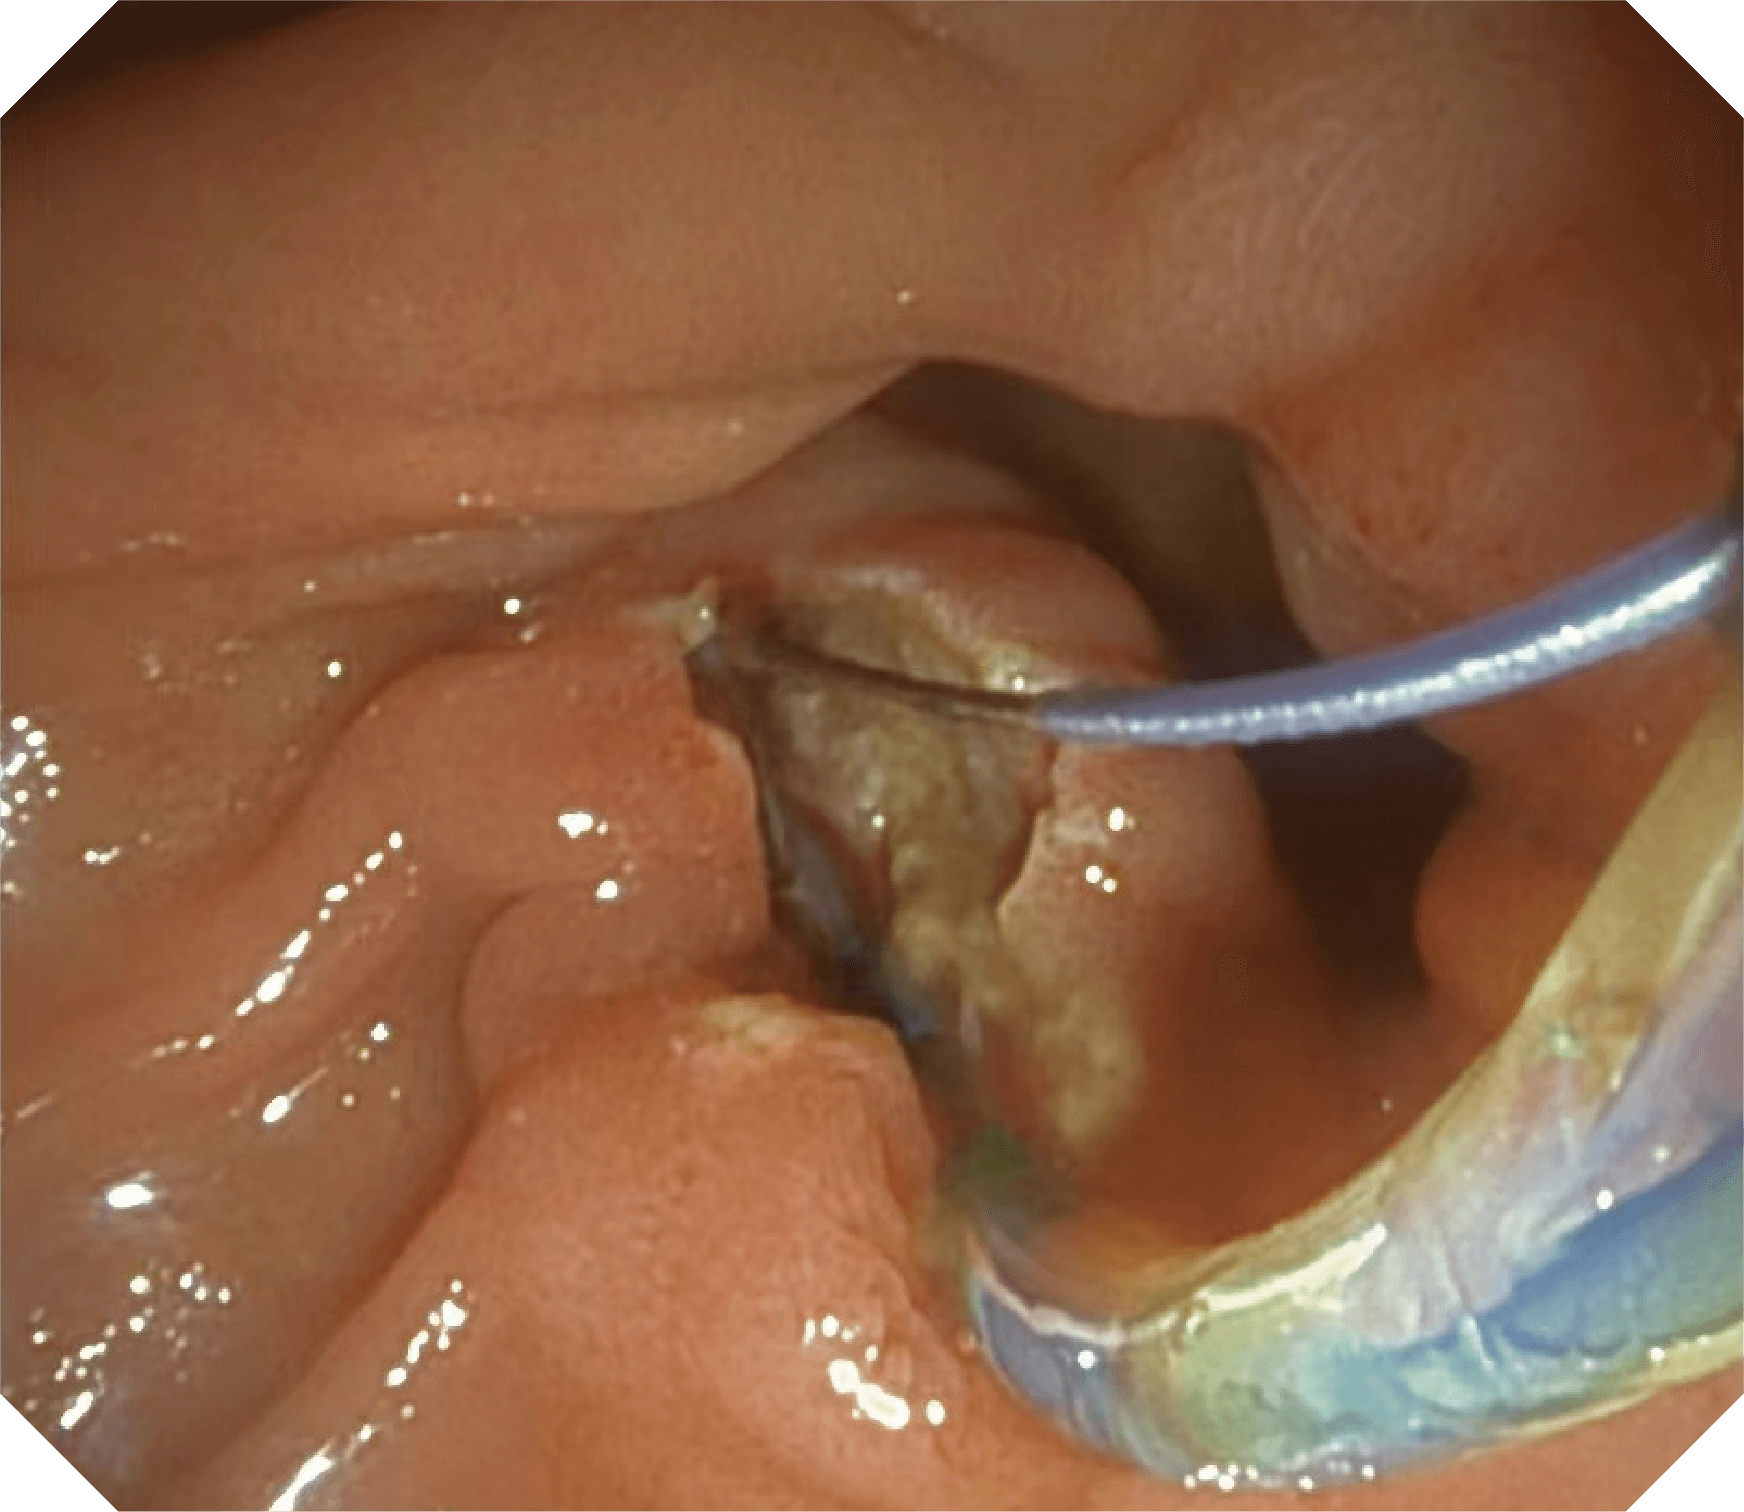

卓越的抬钳器控制

导丝机械锁紧功能

V槽设计提升导丝控制